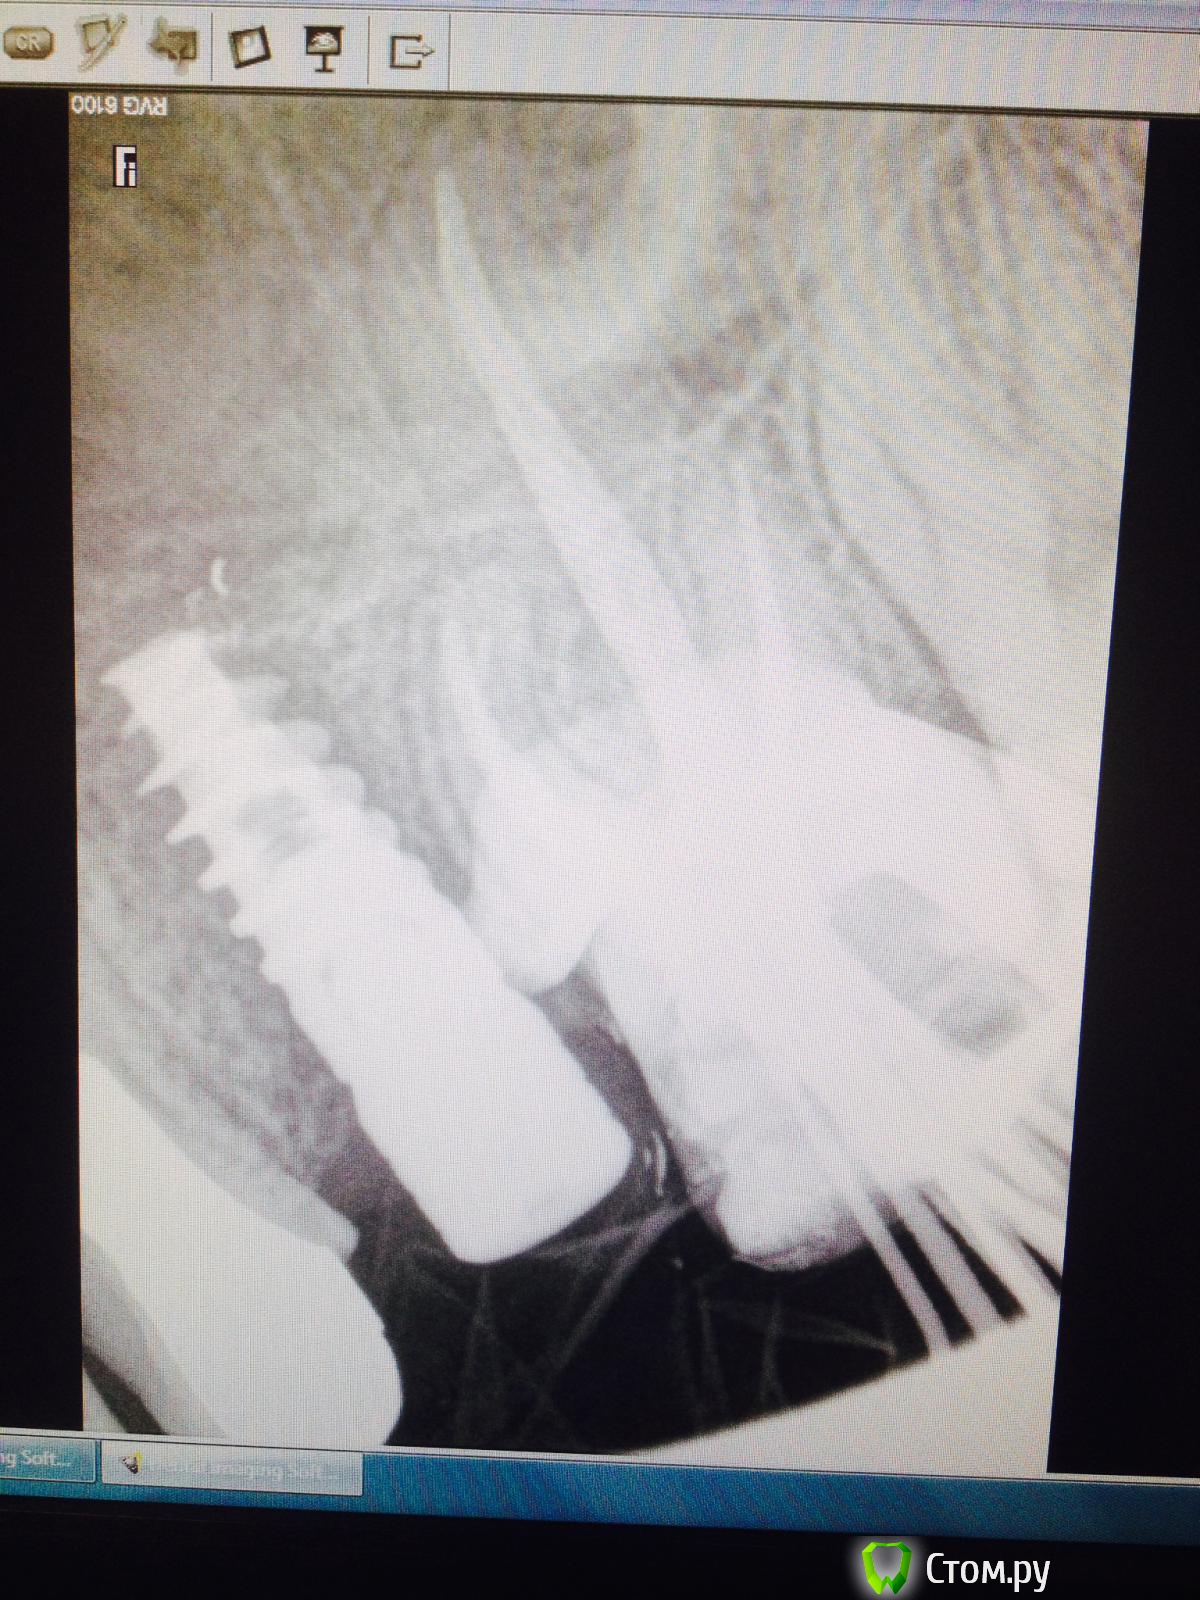

Тимур86 Опубликовано 17 июня, 2014 Поделиться Опубликовано 17 июня, 2014 Господа!пациентке около 4 месяцев тому назад был установлен имплантат в области 25!альфа спи 4.2/10,кт нету под рукой,но проблем с костью небыло вообще (10/10мм по-моему)!в общем имплантация как по учебнику!торк 30-35,сверлил не больше 1000 об.все зажило норм!пришла на фдм-поставили!после установки фдм жаловалась на дикие боли в области импланта!как при пульпите!всю голову сломали,26 по пульпиту пролечили(там пломба глубокая была)в общем вчера,недели через 3 после установки фдм,ортопед вытащил пальцами имплантат...вопросы:1-по какой причине это могло случиться?если дезинтеграция-то почему при установке фдм не вылетел?торк был 30!2-если предположить что боли все-таки были связаны с имплантатом,то что же там так могло болеть на протяжении почти 2- недель? Ссылка на комментарий

КДБ Опубликовано 17 июня, 2014 Поделиться Опубликовано 17 июня, 2014 у меня часто какие-то изменения рентгенологически в первые месяцы!связывал это с ремоделировкой кости...явно носит воспалительный характер и 1 снимок и еще выраженней 3й Ссылка на комментарий

Тимур86 Опубликовано 17 июня, 2014 Автор Поделиться Опубликовано 17 июня, 2014 не может быть причиной материал в гайморовой выведенный? Ссылка на комментарий

Тимур86 Опубликовано 17 июня, 2014 Автор Поделиться Опубликовано 17 июня, 2014 Имею виду боль же появилась до лечения 6 зуба и выведения в пазуху. Значит зуб не при чем.да до лечения,я про материал после удаленного 25! Ссылка на комментарий

Фарид Расулыч Опубликовано 17 июня, 2014 Поделиться Опубликовано 17 июня, 2014 Там очень мало его. И вы бы точно получили симптоматику гайморита а не пульпита. Ссылка на комментарий

GAN Опубликовано 17 июня, 2014 Поделиться Опубликовано 17 июня, 2014 На момент установки ФДМ имплант мог не быть остеоинтегрирован, а якобы стабильность ему придала агрессивная резьба, ФДМ при закручивании провернул его...вот и ушёл винт. Мне SPI принципиально не нравятся как раз из за агрессивной резьбы. А на момент установки могли и фрезы быть тупыми-перегрел кость, когда меняли в последний раз? 5 Ссылка на комментарий

4ebstom Опубликовано 17 июня, 2014 Поделиться Опубликовано 17 июня, 2014 моя версия:возможно фдм при закручивании касался зуба ,те было давление на имплант,соответственно две недели происходила непрерывная нагрузка на имплант.Больше в голову ничего не приходит. 1 Ссылка на комментарий